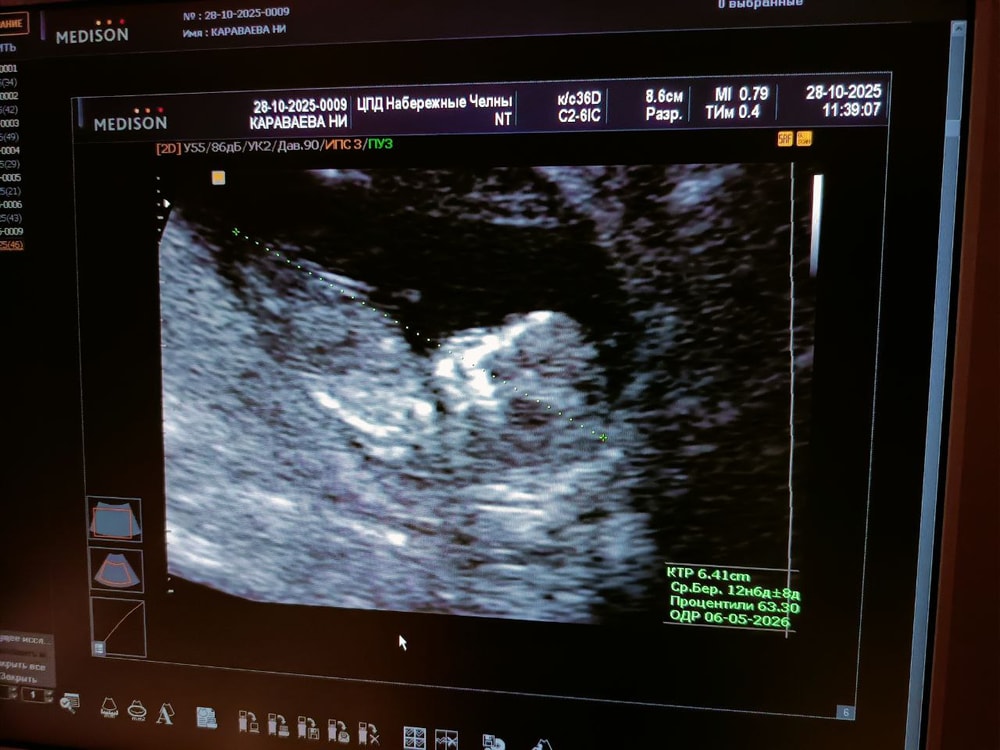

1 скрининг. Попытка 2.

После третьего раза не смогли проверить носовую косточку и ТВП. Хорошо, что остальное смогли увидеть и измерить.

После четвёртого раза всё же смогли измерить оставшееся.

В результате по УЗИ всё-таки всё хорошо. Теперь буду ждать результат крови. Скорее будет высокий риск преэклампсии, но это ожидаемо в моём случае.